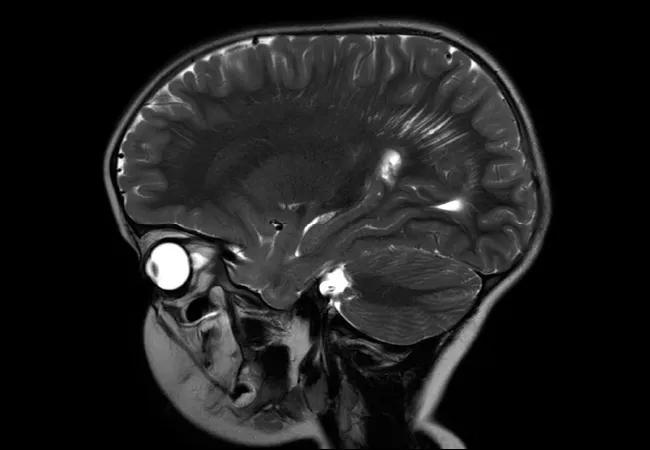

Brain MRI typically shows prominent Virchow-Robin/perivascular spaces with a posterior predominance (Figure 1). Developmental venous anomalies are very common, while high-flow intracranial vascular anomalies such as arteriovenous malformations are uncommon. Cavernomas have also been described. Cerebellar dysplastic gangliocytoma is almost pathognomonic for Lhermitte-Duclos disease, and is rarely seen in children. Lifetime cancer risk is greater than 80 percent, and higher in women than men.

Figure 1. Sagittal (left) and axial (right) T2-weighted images with prominent perivascular spaces showing a posterior predominance in a young child with germline PTEN gene mutation. Images courtesy of Saunder Bernes, MD, Phoenix Children’s Hospital.